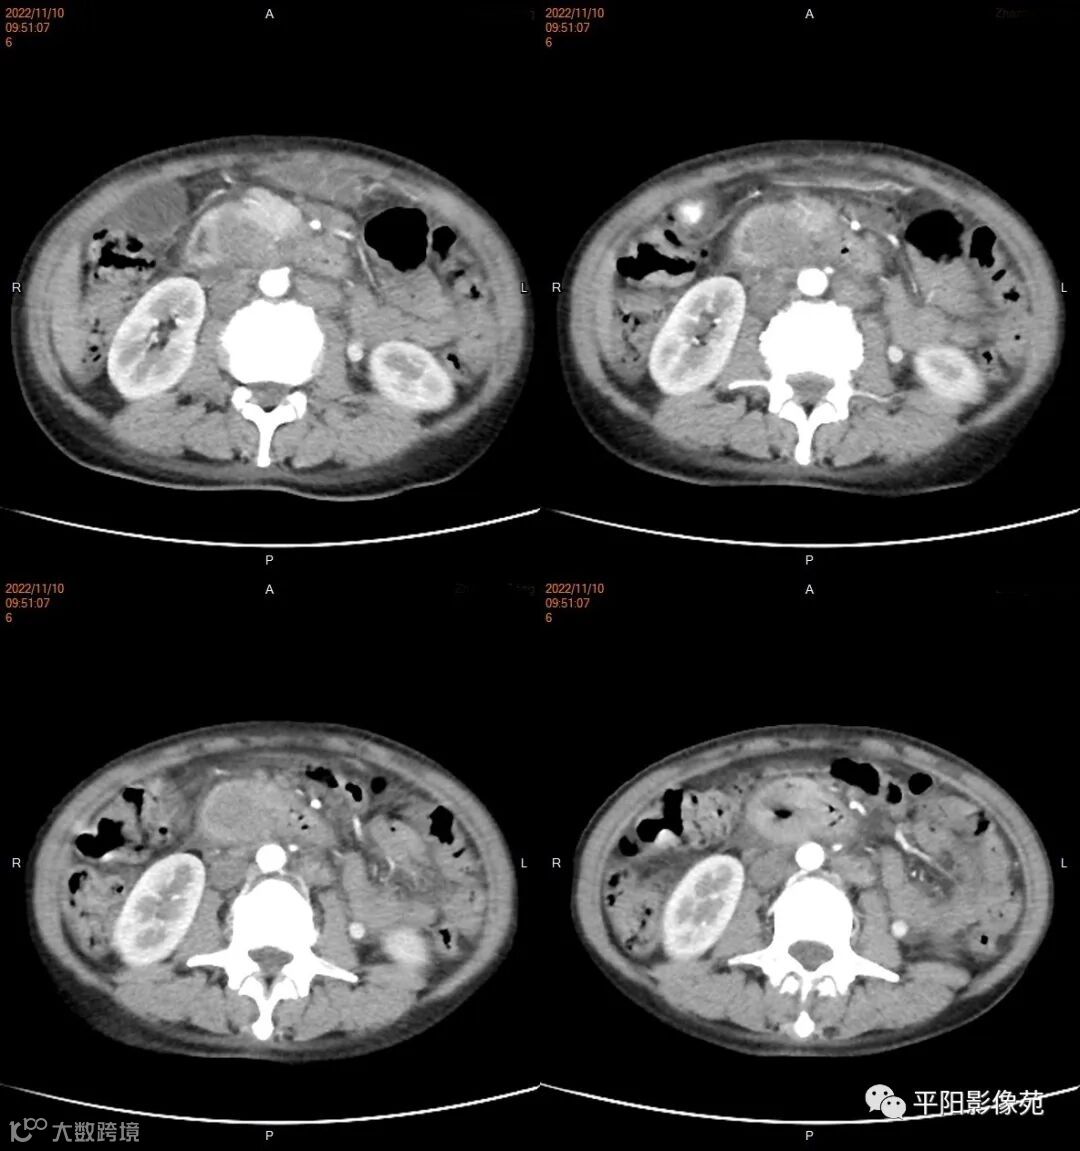

影像学检查

CT

影像表现: